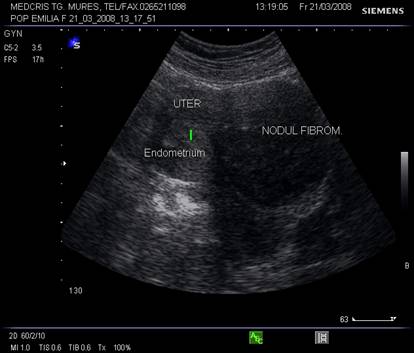

Fibromul uterin - cea mai frecvent intalnita tumora genitala, cu frecventa de 20 - 50% din femei [3].

Aproximativ 90% din fibroame (leiomioame) apar la nivelul corpului uterin. Se descriu, faza miomatozei difuze, fibroame intramurale, subseroase, submucoase, intraligamentare.Mioamele prezinta margini bine delimitate fata de miometru la ecografie, continand arii de mai mare sau mai mica ecogenitate in functie de modificarile degenerative.[1,6]

Fig, nr.380. Nodul fibromatos intramural si subseros al peretelui anterior uterin, in sectiunea sagitala a ecografiei abdominale